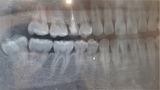

口腔外科では、歯や口腔粘膜だけでなく、顔面や首、頭などの病気、外傷なども治療を行います。親知らずの抜歯、嚢胞摘出、小帯切除、顎関節症治療、歯や口腔内の外傷の治療、顎の骨折の治療や手術、歯が原因の炎症の治療、口や顎の腫瘍の診断なども行います。口腔がん、親知らずの抜歯、お口の中のできもの、腫瘍、口内炎など口腔外科のご相談は、天白区の歯医者 イナグマ歯科までご相談ください。

口腔外科は、口腔や顎に関連する外科的治療を専門とする医療分野です。この分野では、虫歯や歯周病などの一般的な歯科疾患から、外傷、口腔癌、粘液腫、顎関節症まで、さまざまな問題を扱います。口腔外科医は、高度な技術と専門知識を活かして、患者の健康と生活の質を向上させることを目指します。

親知らず、または第三大臼歯は、通常18歳から25歳の間に生えてくる歯で、多くの場合、口腔内に十分なスペースがないためにさまざまな問題を引き起こします。親知らずの抜歯は、口腔外科でよく行われる手術の一つで、以下のような理由で必要とされることがあります。

親知らずは、正しい位置に生えてくることが少なく、斜めに生えたり、隣接する歯を押したりすることがあります。このような場合、歯並びが悪化し、他の歯に悪影響を及ぼすことがあるため、抜歯が推奨されます。

親知らずは、磨きにくい位置にあるため、虫歯や歯周病のリスクが高まります。特に、部分的に生えている親知らずは、周囲の歯や歯肉に感染を引き起こす可能性があります。このような状態になった場合、早期に抜歯することが望ましいです。